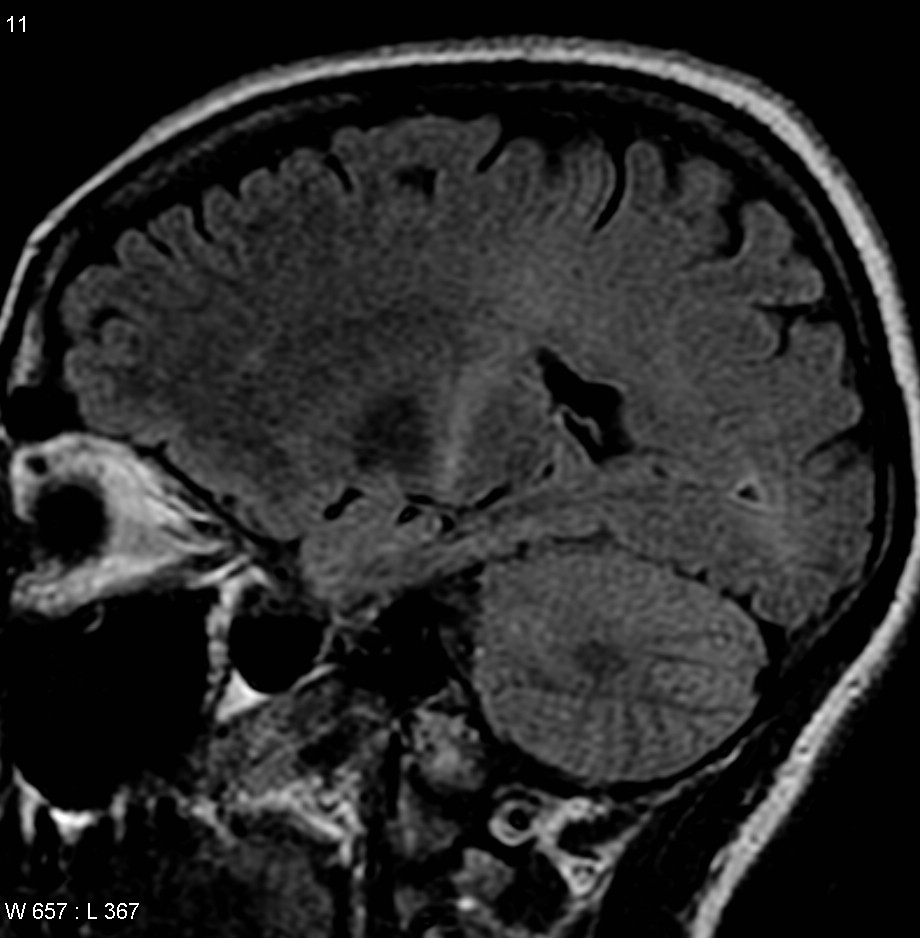

루게릭병 증세를 보이는 환자의 MRI 사진 by Frank Gaillard CC-BY-SA 3.0(Wikimedia commons)